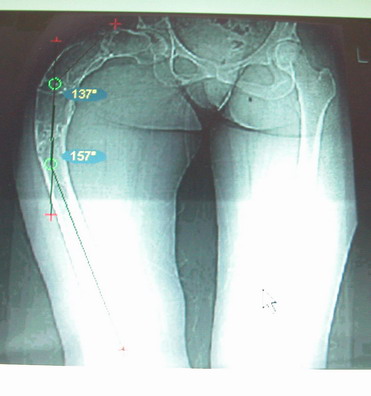

Моё мнение, что двойная остеотомия бедра с аппаратом Илизарова + Гексаподный механизм, или Тэйлора, В данной ситуации является методом выбора. Я очень извеняюсь за качество прилагаемых снимков, в которых я постарался отразить разницу междe одной и двумя остеотомиями бедра.

Хотелось бы показать, что получилось в результате.

Операция выполнялась с помощью А.Н.Челнокова. Очень понравилась технология выполнения блокируемого остеосинтеза с использованием спицевого дистрактора, модифицированный гвоздь с латерализованным проксимальным отделом и возможностью многовинтовой фиксации проксимального и дистального участков бедра.